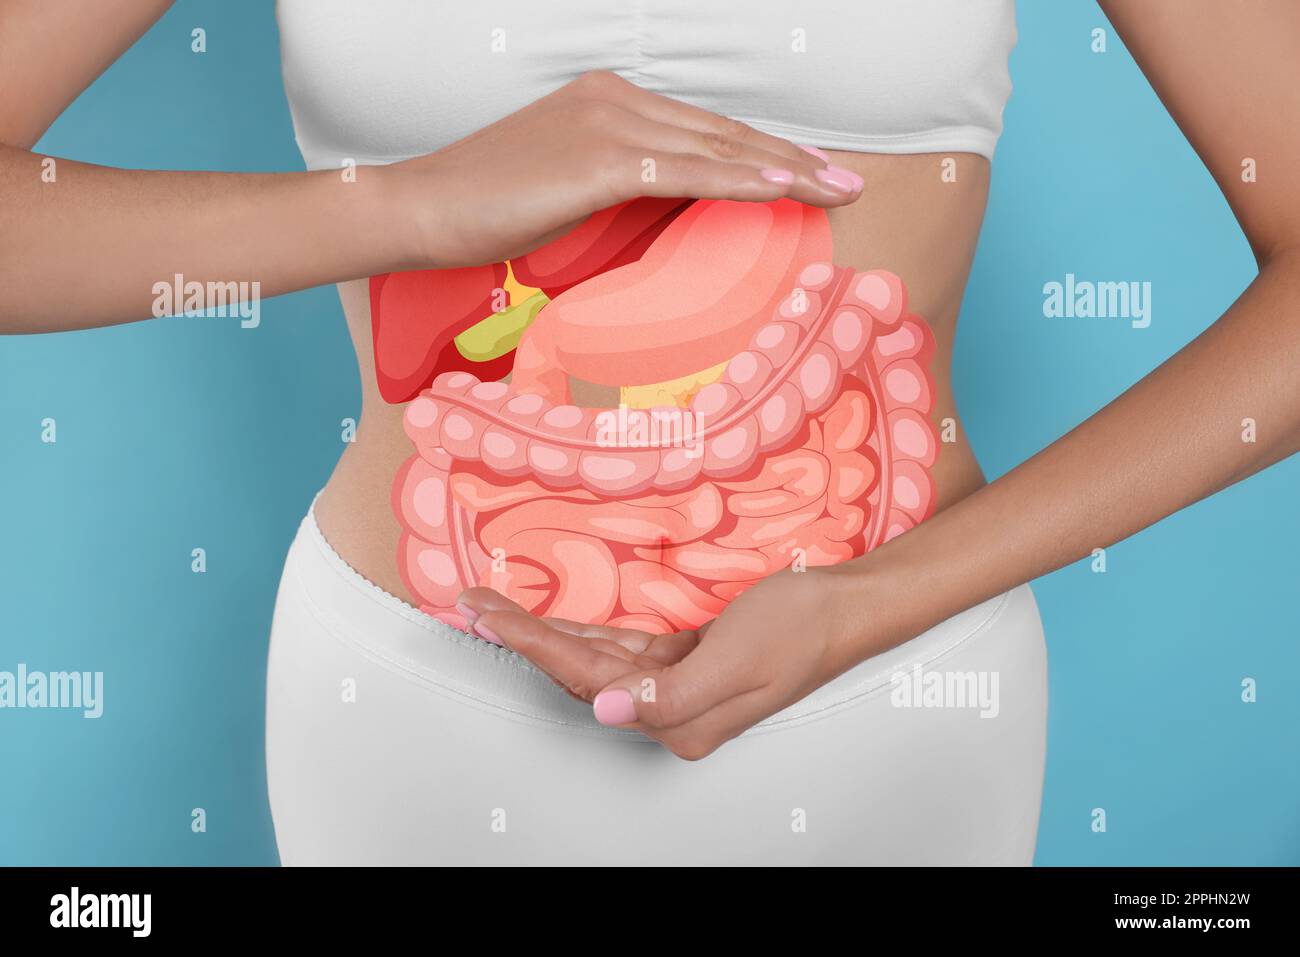

Vue rapprochée de la femme avec illustration des organes abdominaux sur son ventre sur fond bleu clair Banque D'Imageshttps://www.alamyimages.fr/image-license-details/?v=1https://www.alamyimages.fr/vue-rapprochee-de-la-femme-avec-illustration-des-organes-abdominaux-sur-son-ventre-sur-fond-bleu-clair-image547433569.html

Vue rapprochée de la femme avec illustration des organes abdominaux sur son ventre sur fond bleu clair Banque D'Imageshttps://www.alamyimages.fr/image-license-details/?v=1https://www.alamyimages.fr/vue-rapprochee-de-la-femme-avec-illustration-des-organes-abdominaux-sur-son-ventre-sur-fond-bleu-clair-image547433569.htmlRF2PPHN2W–Vue rapprochée de la femme avec illustration des organes abdominaux sur son ventre sur fond bleu clair